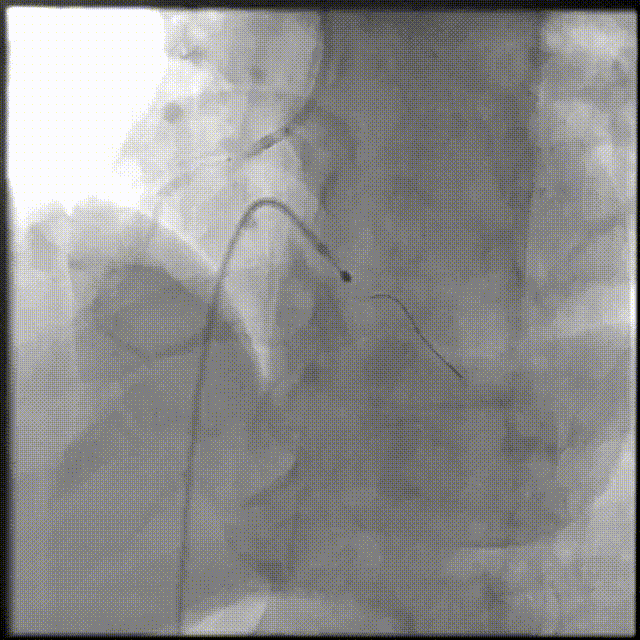

PCI过程-冠状动脉旋切(轨道旋磨)术-1

IVUS导管无法通过,微导管辅助下,将旋磨导丝置于RCA远端,应用1.0mm磨头以13万转反复旋磨钙化病变处(每次15秒,磨头推进速度不超过10 mm/s)

PCI过程-冠状动脉旋切(轨道旋磨)术-2

微导管辅助下,将旋磨导丝置于RCA远端,应用1.0mm磨头以13万转反复旋磨钙化病变处(每次15秒,磨头推进速度不超过10 mm/s)

PCI过程-冠状动脉旋切(轨道旋磨)术-3

共计旋切170秒,术后,狭窄较前减轻